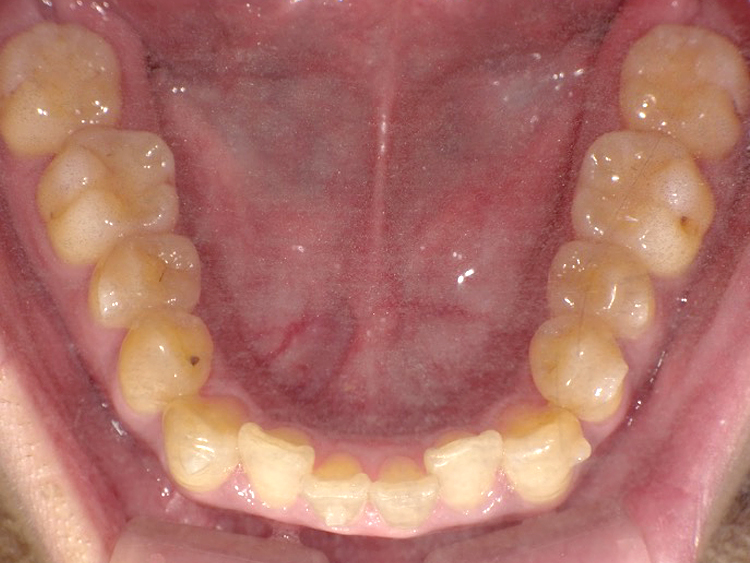

症例4

Before

After

| 主訴 | 上下前歯のがたつき |

|---|---|

| 年齢 | --- |

| 治療 期間 |

約9ヶ月 |

| 治療 内容 |

インビザラインiGoで上下顎の治療。 |

| 治療費 | ¥550,000(税込)/調整料含む |

| 治療のリスク | 矯正終了後は、リテーナーを指示通りに使用し、歯の後戻りを防ぐ必要があります。 |